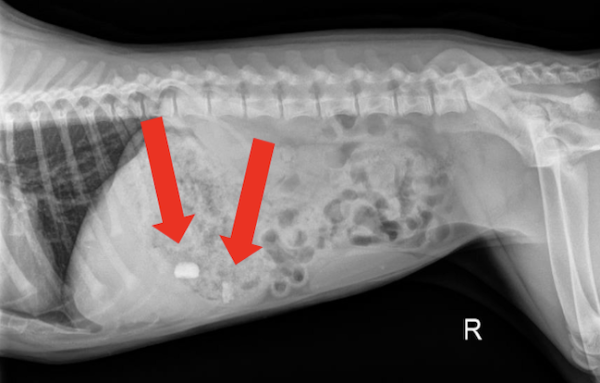

Radiograph findings:

The radiographs returned two radiopaque foreign materials in the stomach (shown above by the red arrows). These objects were suspected to be rocks. In order to confirm the location of these objects two views were taken including the lateral views above as well as a ventrodorsal (VD) view (not pictured).

Foreign bodies in the stomach. One large rock, and one smaller rock near the pylorus. The smaller rock was more concerning due to its location at the pylorus and the potential for it to become lodged at this location or pass into the duodenum.